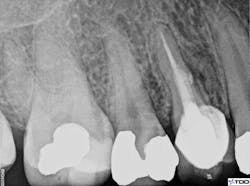

The patient was seen for a two-week recall, at which point the draining sinus tract was no longer present. The tooth was asymptomatic, and the clinical exam was within normal limits. The restorative dentist placed a composite core in the occlusal access one week later. Six-month recall showed radiographic evidence of healing (figure 6). At that time, the clinical exam was within normal limits. The patient remains asymptomatic.

Figure 6: Radiographic evidence of healing at six-month recall